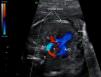

Al nacimiento se confirma el diagnóstico por ecocardiograma transtorácico (ETT) y se realiza seguimiento semestral. En el plano supraesternal corto se objetiva anillo vascular rodeando la tráquea (fig. 2A). El plano supraesternal largo, demuestra arco derecho dominante e izquierdo hipoplásico (fig. 2B). Se realiza tomografía computarizada multicorte (TCMC) que define de forma precisa la anatomía vascular (fig. 3A-C) y muestra impronta traqueal con estenosis leve de su diámetro transverso (fig. 3D).